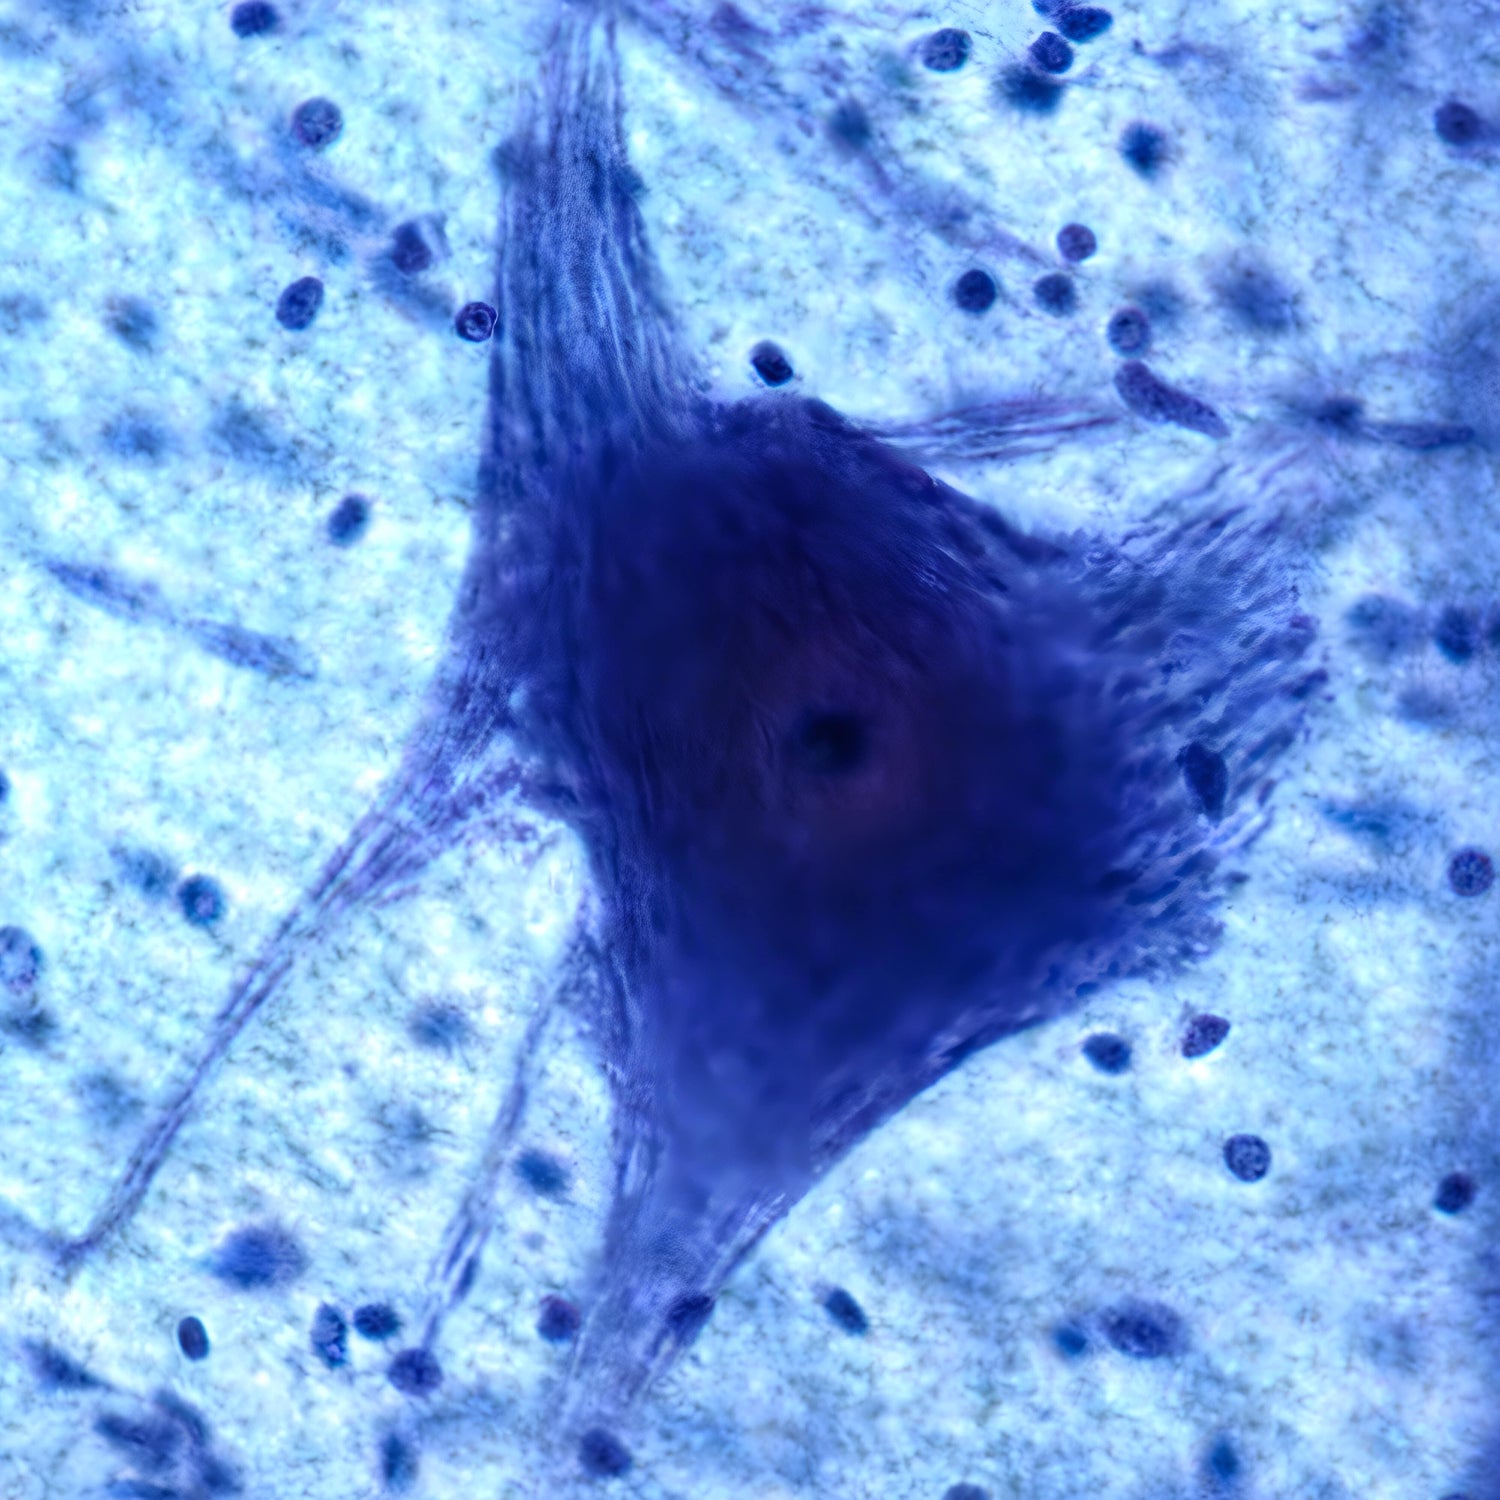

COLLOIDAL SILVER

Learn MoreSilver nanoparticles hold immense promise as therapeutic agents for various medical applications. Their unique properties, including broad-spectrum antimicrobial activity, wound healing potential, and drug delivery capabilities make them attractive candidates for innovative medical interventions.